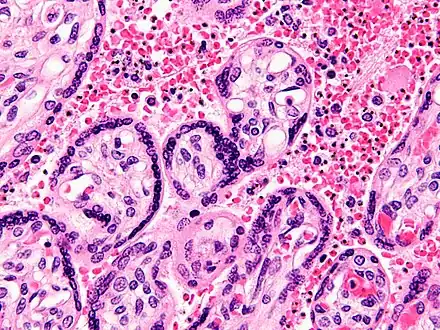

The blood film is the gold standard for malaria diagnosis.

Ring-forms and gametocytes of Plasmodium falciparum in human blood